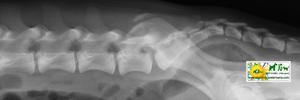

![]() por Juan M. Griñán. Veterinario ![]() comparativa entre una mielografía (mostrando la aguja) y una resonancia magnética, secuencia SE T1w (mostrando donde está el saco dural, sitio para la inyección del contraste). Nótese la extravasación del contraste yodado en la mielografía. | |||||||||